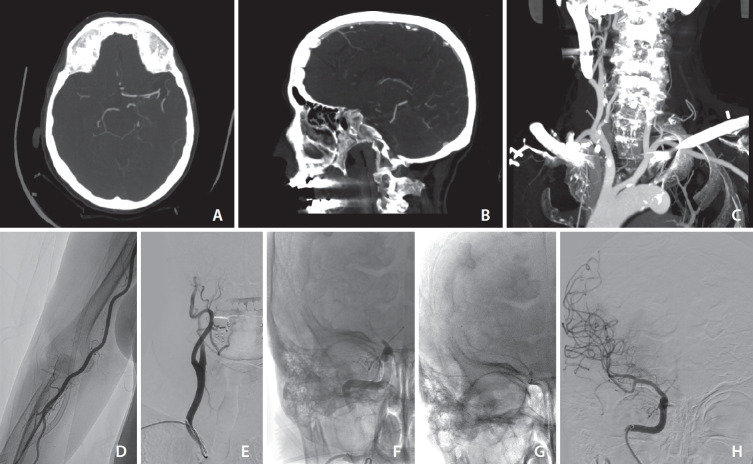

Results: Of 20 patients selected, 10 (50%) had occlusion of M1 segment of middle cerebral artery (MCA), 6 (30%) of internal carotid artery (ICA) terminus, and 4 (20%) with M2 MCA occlusions; 12/20 (60%) were right-sided occlusions and 8/20 (40%) were left-sided. The mean National Institutes of Health Stroke Scale score was 9.25 at admission. Successful revascularization to mTICI 2b-3 was achieved in 18/20 patients (90%). Intracranial complications were reported in 2 (10%) patients. Rate of radial artery occlusion at 24 hours was 10,6%; no access-site haemorrhagic complications were reported. Symptomatic intracranial hemorrhage occurred in 2 (10%) patients. mRS score 0-2 at 3 months was 50%.

Abstract Image